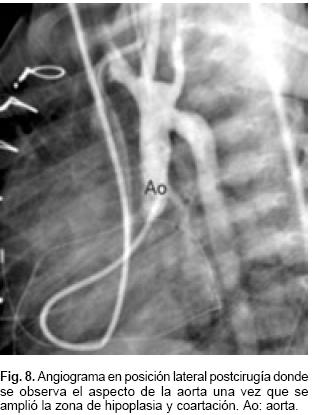

La niña fue llevada a tratamiento quirúrgico, se realizó resección de la porción hipoplásica de la aorta con reconstrucción mediante anastomosis términoterminal extendida, sección y sutura del conducto arterioso, además de cerclaje de la arteria pulmonar con colocación de una banda de 6 mm. Diez días después de la cirugía por falla cardíaca se llevó a cateterismo de control y se demostró que no había obstrucción residual en la aorta (Fig. 8), la PSAP de 40 mm Hg, la presión del ventrículo izquierdo era de 85 mm Hg y el gradiente subaórtico de 30 mm Hg. Egresó a casa en buenas condiciones generales a las 6 semanas de cirugía; con el plan de realizar alrededor del año de edad corrección de la doble salida del ventrículo derecho.